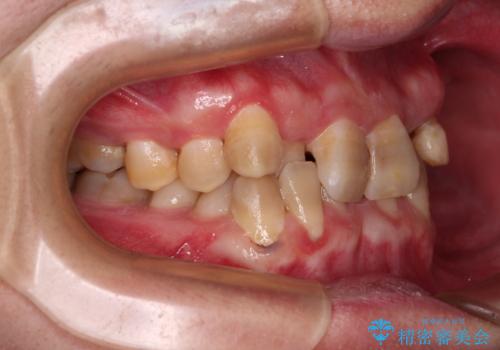

上顎が側方に拡大されて歯が並ぶスペースを確保できました。

それに伴い下顎の歯列も拡大され、舌側に倒れているのが改善されました。